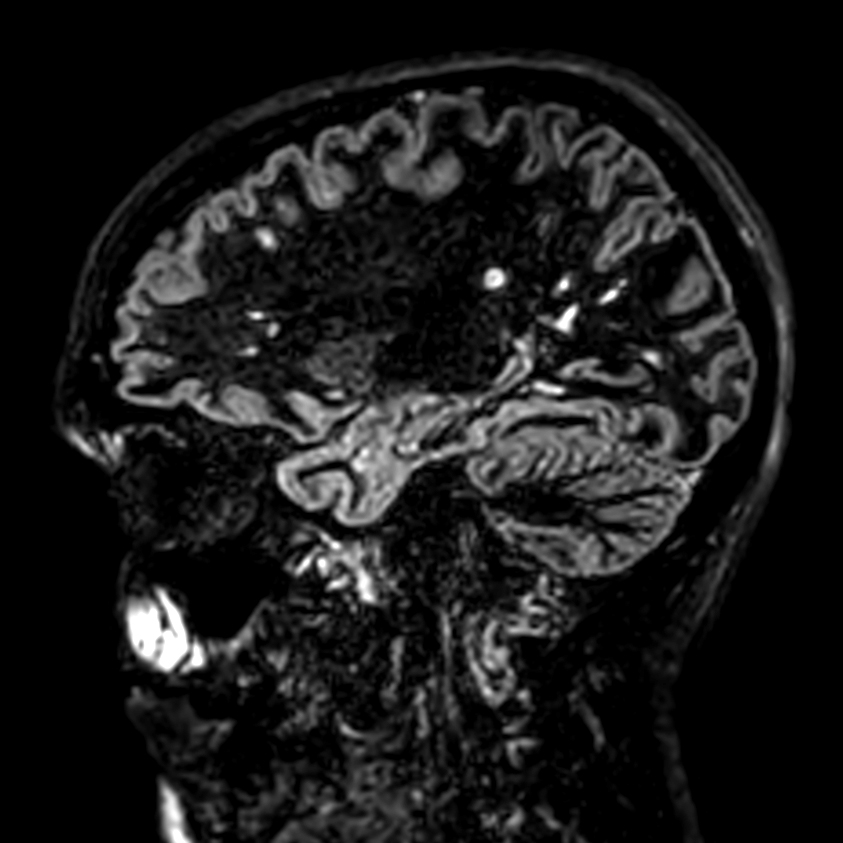

Patient with multiple brain lesions. ExamCard includes Compressed SENSE to shorten the exam time, 3D scans to acquire high resolution data in multiple directions in only one single scan and 4D-TRAK for dynamic contrast-enhanced MR Angiography enabling high spatial and temporal resolution simultaneously.

DWI (b1000)